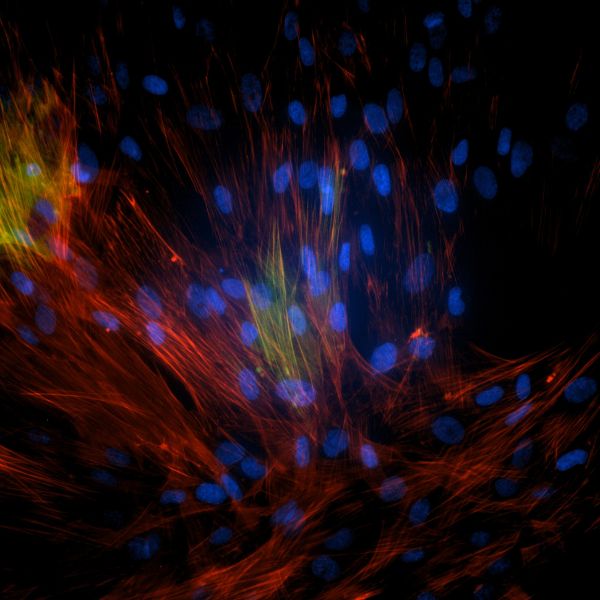

Lung cells grown in research lab that have become fibrotic